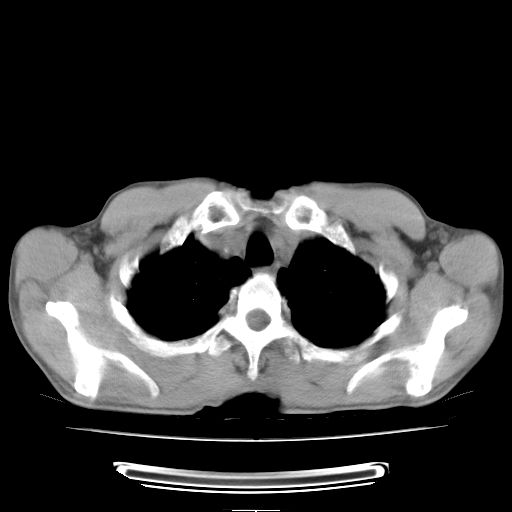

标题: CT25795:感冒后反复咳嗽两月余,痰中带血半月余。X诊断“肺 [打印本页]

标题: CT25795:感冒后反复咳嗽两月余,痰中带血半月余。X诊断“肺

1.双肺肺梗塞(理由:病灶呈三角形,与胸膜相连且局部胸膜肥厚,左心室增大)伴肺感染。

肺梗塞虽然有创意,但不现实。我考虑感染性病灶。

考虑两肺感染性病变,左肺上叶舌段肿瘤性病变待排;建议抗炎治疗后复查。